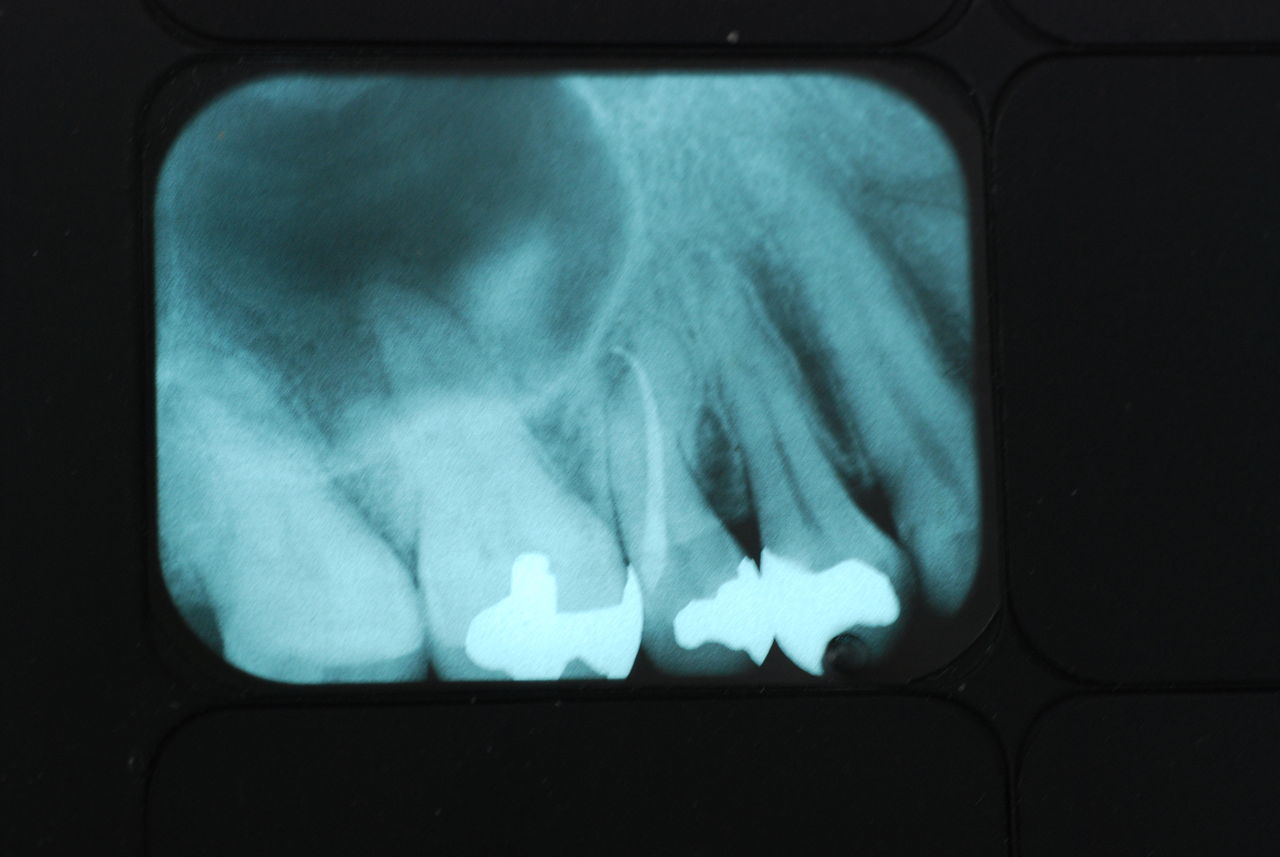

30代の男性の方です。

入れ歯を入れていました。歯科医院で歯を抜けず仕方なく入れ歯にしたとか。何とかならないものだったのか悔やまれました。

抜いた歯はありません。

一応差し歯にしましたが、歯茎の状態はよくはありません。

とりあえず希望を入れて差し歯にしたような感じです。